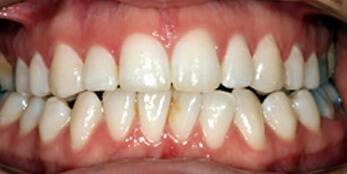

See the smiles we have transformed